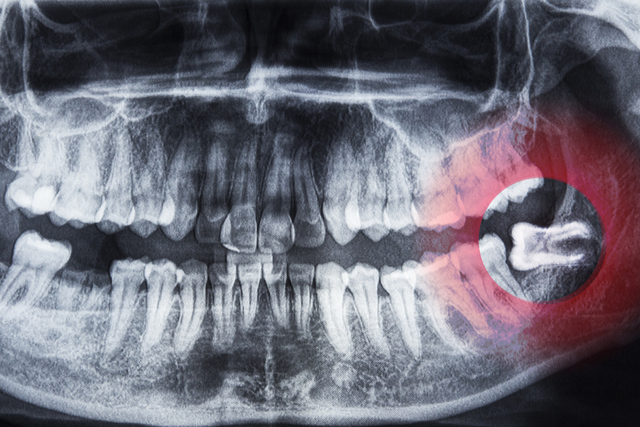

YİRMİLİK DİŞ

İnsan türü, Afrika'dan göç ederek farklı habitatlarda yaşamaya başladı ve zamanla insan uygarlıkları gelişti. Bu süreçte, yumuşak ve işlenmiş gıdalar tüketilmeye başlandı. Bu değişim, büyük ve güçlü çenelere olan ihtiyacı azalttı. Çene boyutunun küçülmesiyle birlikte, özellikle üçüncü azı dişleri veya yirmilik dişler gibi azı dişleri, gömülü kalmaya yatkın hale geldi. Giderek artan bir şekilde, yirmilik dişlerin doğuştan eksik olduğu gözlemleniyor. Sonuç olarak, bu durum artık insan vücudunun körelmiş bir özelliği olarak kabul ediliyor.